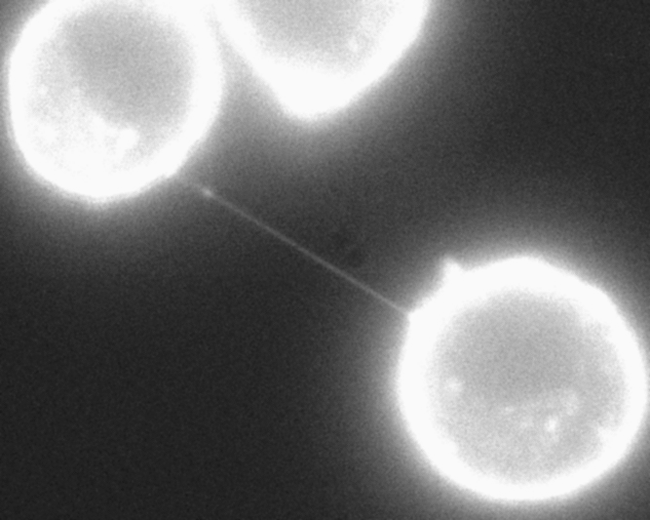

Člani ameriške raziskovalne skupine so preučevali interakcije med rakavimi in imunskimi celicami, pri tem pa so celice raka dojke inkubirali skupaj z različnimi imunskimi celicami. Z elektronsko mikroskopijo so opazili, da so bile rakave in imunske celice po skupni inkubaciji fizično povezane s cevkami, ki v premeru meriju nekaj nanometrov.

Razne celice si lahko po tovrstnih nanocevkah izmenjujejo snovi, pa tudi organele. Predhodno je bilo pokazano, da si celice povrhnjice po takih cevkah izmenjujejo tudi mitohondrije, ki celice preskrbujejo z energijo. Pri nekaterih rakih je bila opažena povezava med povečanjem števila mitohondrijev in napredovanjem tumorja ter razvojem odpornosti proti kemoterapiji. Zato so znanstvenice in znanstveniki mitohondrije v imunskih celicah obarvali s fluorescenčnim barvilom, nato pa so jih inkubirali skupaj z rakavimi celicami. Po nekaj urah so fluorescenčni signal opazili tudi v rakavih celicah. V nadaljevanju raziskave so obarvali mitohondrije v rakavih celicah. Mitohondriji so le redko potovali v nasprotni smeri, torej iz rakavih celic v imunske. To nakazuje, da je potovanje mitohondrijev pretežno enosmerno, in sicer iz imunskih celic v tumorske.